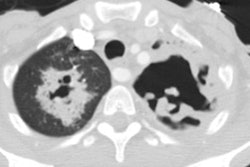

CXR demonstrates migratory infiltrates, but after 1 to 2 months the lesions become stable nodules or cysts predominantly in the lower lobes. Pleural effusions can be seen.CT findings include poorly marginated peripheral or subpleural nodules measuring approximately 2cm (up to 74% of cases) with surrounding ground-glass and a streaky opacity connecting the nodule to the pleural surface [3], pleural effusion, hydropneumothorax, airspace consolidation, and thin walled cysts [1,2].